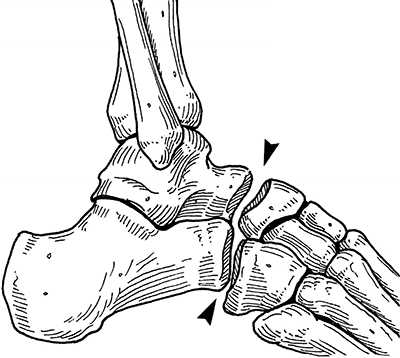

Анатомия повреждения сустава Лисфранка.

Выделяют такие анатомические структуры как связка Лисфранка, сустав Лисфранка и суставной комплекс Лисфранка. Суставной комплекс Лисфранка состоит из предплюсне-плюсневых суставов, межплюсневых суставов, межпредплюсневых суставов.

Наиболее важным моментом в понимании повреждений сустава Лисфранка является осознание критической роли связки Лисфранка в стабилизации не только второго предплюсне-плюсневого сустава но и поддержке всего подошвенного свода. Связка Лисфранка состоит из трёх пучков и связывает медиальную клиновидную кость с основанием второй плюсневой кости. Связка Лисфранка препятствует избыточной пронации и абдукции стопы.

В образовании суставного комплекса Лисфранка также участвуют подошвенные предплюсне-плюсневые связки, тыльные предплюсне-плюсневые связки, межпредплюсневые связки.

За счёт большого количества связок и особенностей строения суставов, суставной комплекс Лисфранка является крайне стабильным с небольшой амплитудой движений.